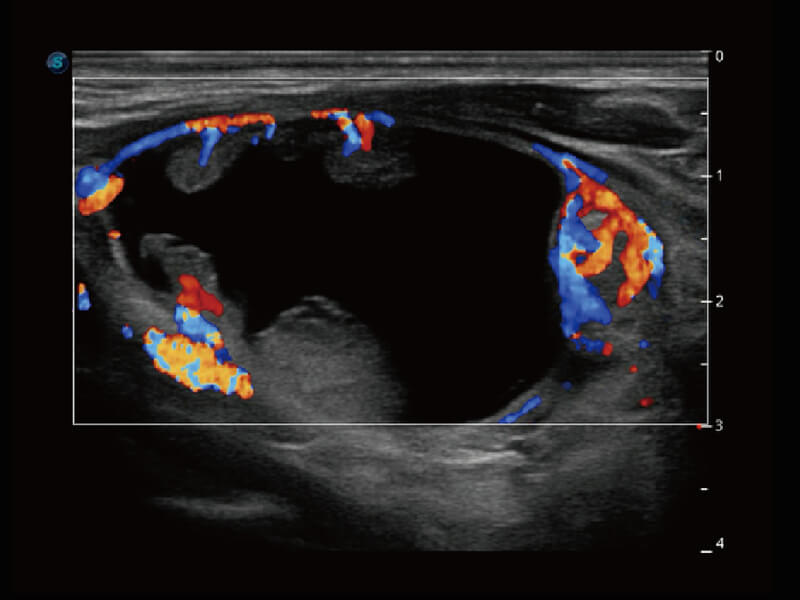

• 新型复合材料探头( 12L-A )

Micro F 显微血流成像 明察秋毫